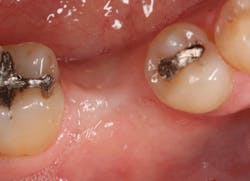

JC is a 57-year-old female with a retained primary tooth K and a congenitally missing No. 20. K was becoming increasingly mobile and developed bone loss beyond the apex of the distal root, necessitating removal of the tooth.

Excellent interseptal bone width was present, both buccal and lingual plates were present, and an adequate amount of bone was present coronal to the inferior alveolar nerve to allow for immediate implant placement. A sulcular incision was made around K and the adjacent teeth, and a full-thickness buccal and lingual flap was reflected. The tooth was sectioned in half, and the mesial and distal roots were elevated. The socket was degranulated with a round diamond bur and copiously irrigated with chlorhexidine gluconate 0.12% rinse. An osteotomy was completed in the interseptal area, and a bone-level 4.8- x 10-mm implant was placed to 35 Ncm. A mixture of cancellous and cortical allograft was infused with autogenous plasma-rich growth factor (PRGF), which was isolated during a preprocedural blood draw. The mixture was packed into the residual socket, slightly coronal to the implant platform to account for predictable resorption during healing. (13)